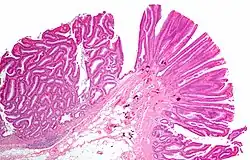

![]() Gruczolak cewkowo-kosmkowy |

Stanowią około 20-25% łagodnych guzów jelita cienkiego. Dzieli się je na gruczolaki prawdziwe, gruczolaki kosmkowe i gruczolaki z gruczołów Brunnera[5]. Zwykle są to zmiany bezobjawowe; mogą jednak powodować krwawienie z przewodu pokarmowego lub niedrożność. Gruczolak ma pewien potencjał do złośliwienia i podobnie do gruczolaków jelita grubego gruczolaki kosmkowe charakteryzuje większa skłonność do złośliwienia[1].